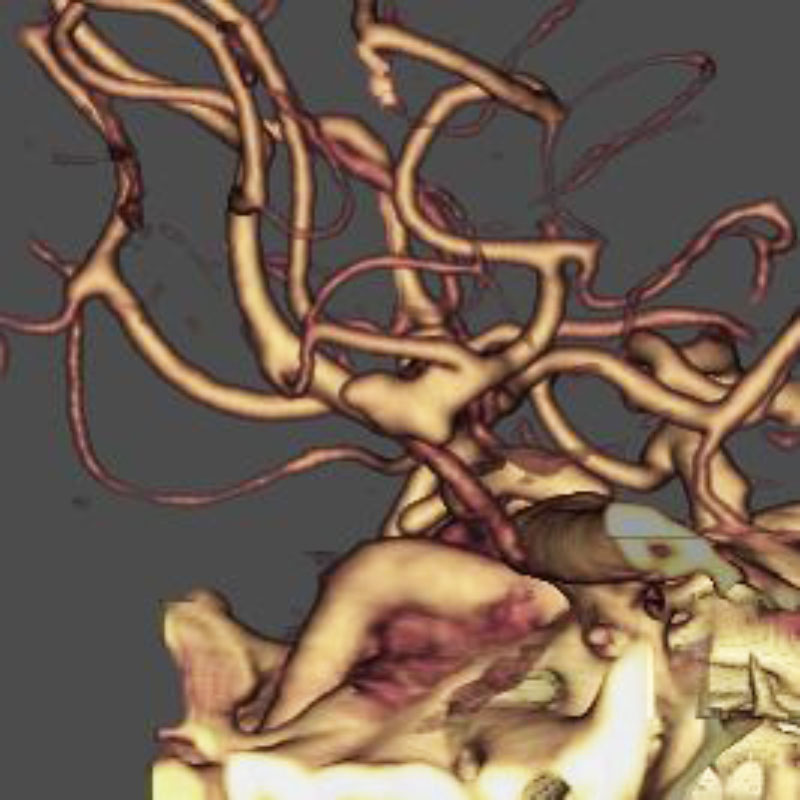

脳動静脈奇形

血管塞栓術

松田/濵田/元永